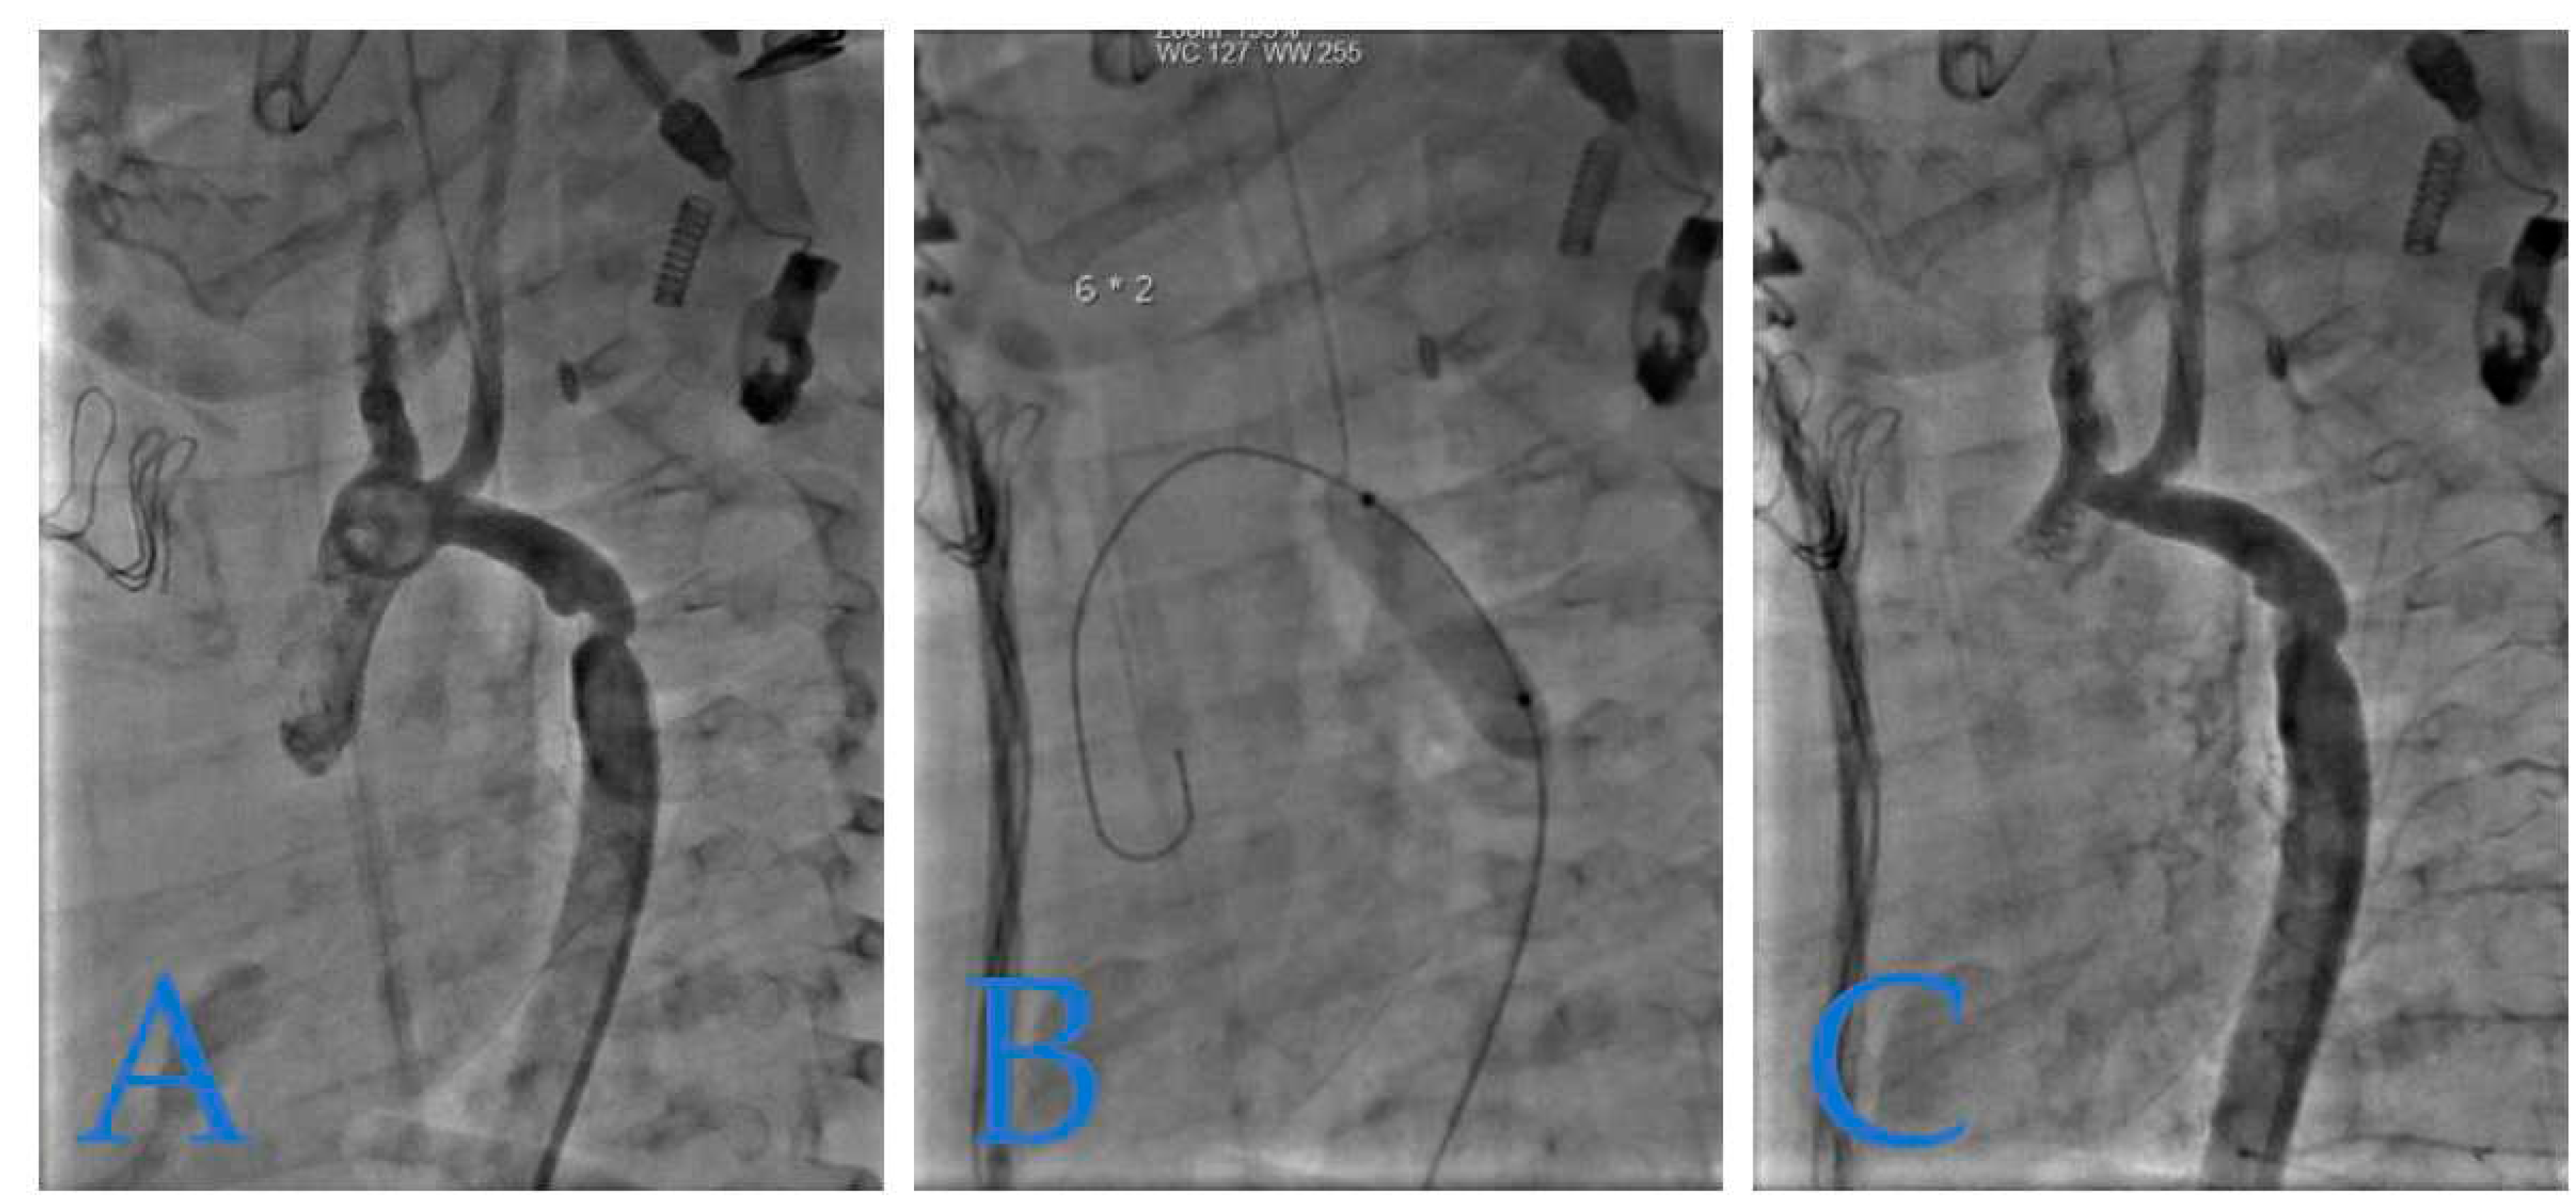

Figure 5 depicts recoarctation in a 4-month-old infant weighing 4.8 kg. The patient had previously undergone treatment for tight isthmic coarctation using the Waldhausen procedure at 14 days of life following cardiogenic shock. Notably, the left sub-cardiac artery was absent in this case.

Figure 6 presents a case of isthmic recoarctation in a 3-year-old patient weighing 12 kg. The patient had previously undergone a Crafoord extended procedure at 16 days of age.

Figure 5. Infant Recoarctation After Initial Repair. (A): The recoarctation is measured at 3.7 mm, in the context of a horizontal aorta measuring 5.3 mm and a descending aorta of 7.1 mm. The trans-recoarctation gradient is 30 mmHg. (B): Treatment involved a 6x20 mm Tyshak balloon dilatation. (C): Subsequent angiography shows an isthmus diameter of 5.5 mm with no residual gradient, indicating a successful outcome.

Figure 6. Toddler's Recoarctation After Initial Repair. (A): The isthmus, measuring 5.4 mm within a descending aorta and aortic arch of 9.4 mm, is shown before dilatation. (B): Dilatation was achieved using an 8x20 mm Tyshak balloon. (C): Post-dilatation control angiography indicates a successful outcome with an isthmus diameter of 7 mm.